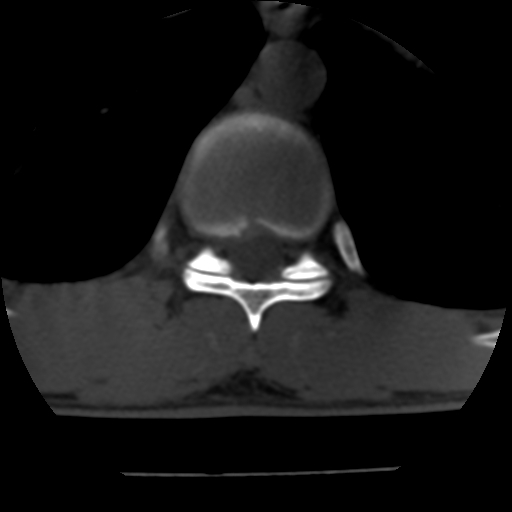

标题: CT10387:男,31岁,胸腰段CT [打印本页]

男,31岁,从6米高处坠落伤两天,腰背部疼痛,临床要求ct扫描胸10-腰1。请大家帮忙看看骨质有问题吗?

t12、l1锥体前缘轻度楔形变,平扫示椎体前缘骨小梁欠规整,第9幅图示椎体前缘骨质不连续,结合外伤史考虑椎体轻度压缩骨折。

楼主扫描层厚可能较大,每个椎体只有三个层面.

从所示层面分析,无明确骨折征象,象类似病人我个人会建议mri除外骨挫伤.

从上查骨窗第九片椎体前缘皮质显示断裂.压缩骨折?